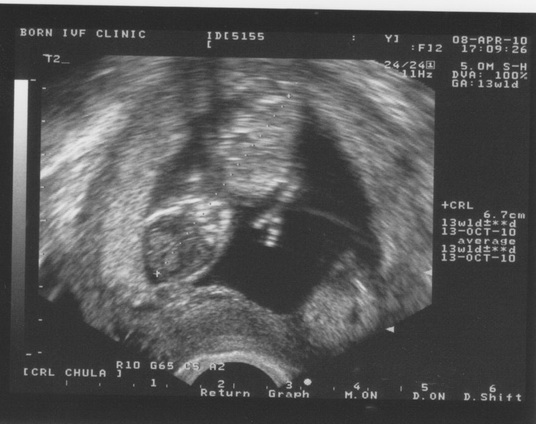

week ที่ 13

อาทิตย์นี้เราได้มาเจอกันอีกครั้งนะเจ้าตัวน้อยทั้งสอง โชคดีที่อาทิตย์นี้พ่อมีประชุมที่กรุงเทพฯวันศุกร์ ทำให้พ่อไม่ต้องขับรถ ไป-กลับ ลพบุรี- กทม. หลายรอบเหมือนทุกครั้ง(รอบนี้สบายเลย 555+)

ผลการตรวจ อาทิตย์นี้ เจ้าตัวน้อยทั้งสอง โตขึ้นมาก เห็นขาเห็นขาชัดขึ้น เริ่มเห็นแนวกระดูกสันหลัง (มีแอบโบกมือ ให้พ่อกับแม่ดูด้วย รอบนี้ 555+) แข็งแรงดีทั้งคู่ พ่อกับแม่รู้สึกดีความสุขอย่างมากทุกครั้ง ที่ได้เห็นการขยับตัว ขยับแข้ง ขยับขา ของเจ้าตัวเล็กทั้งสอง

ส่วนทางคุณแม่ดีขึ้นเยอะเลย คุณหมองด ยาสอดกับ ยาทานที่เสริม ฮอร์โมน รวมทั้งไม่ต้องฉีดยา แล้ว ทำให้การคลื่นไส้ของคุณแม่ ลดน้อยลงไปเยอะ ส่วนการนัดอีกครั้ง รอบนี้ เป็นอีกหนึ่งเดือนถัดไป (รอบการนัดตรวจเริ่มนานขึ้นละ คุณหมอบอกว่า เจ้าหนูทั้งสองแข็งแรงดี มาก ทำให้พ่อกับแม่ สบายใจขึ้นมากมายเลย)